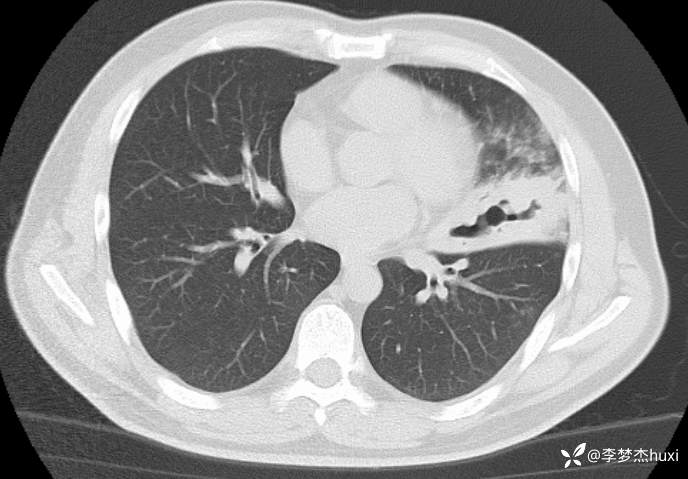

男性40岁,咳嗽、咳痰5天,CT示空洞病变,可能是啥病原菌?

【现病史及既往史】: 1.患者中年 男,患者缘于5天前前无诱因出现咳嗽、咳痰,为黄痰,伴臭味,痰不易咳出,伴发热,最高体温不详,无喘息、憋气,无胸痛,无咯血,无腹痛腹泻,无恶心、呕吐。院外未应用药物治疗,症状无明显好转,为求进一步治疗来院就诊,门诊查胸部CT;双肺炎症,左肺上叶厚壁空洞形成,双肺纹理增重,双侧胸膜局限性增厚,脂肪肝,建议结合临床复查。以“肺炎”收住院;。

【临床诊断】:肺脓肿伴有肺炎。